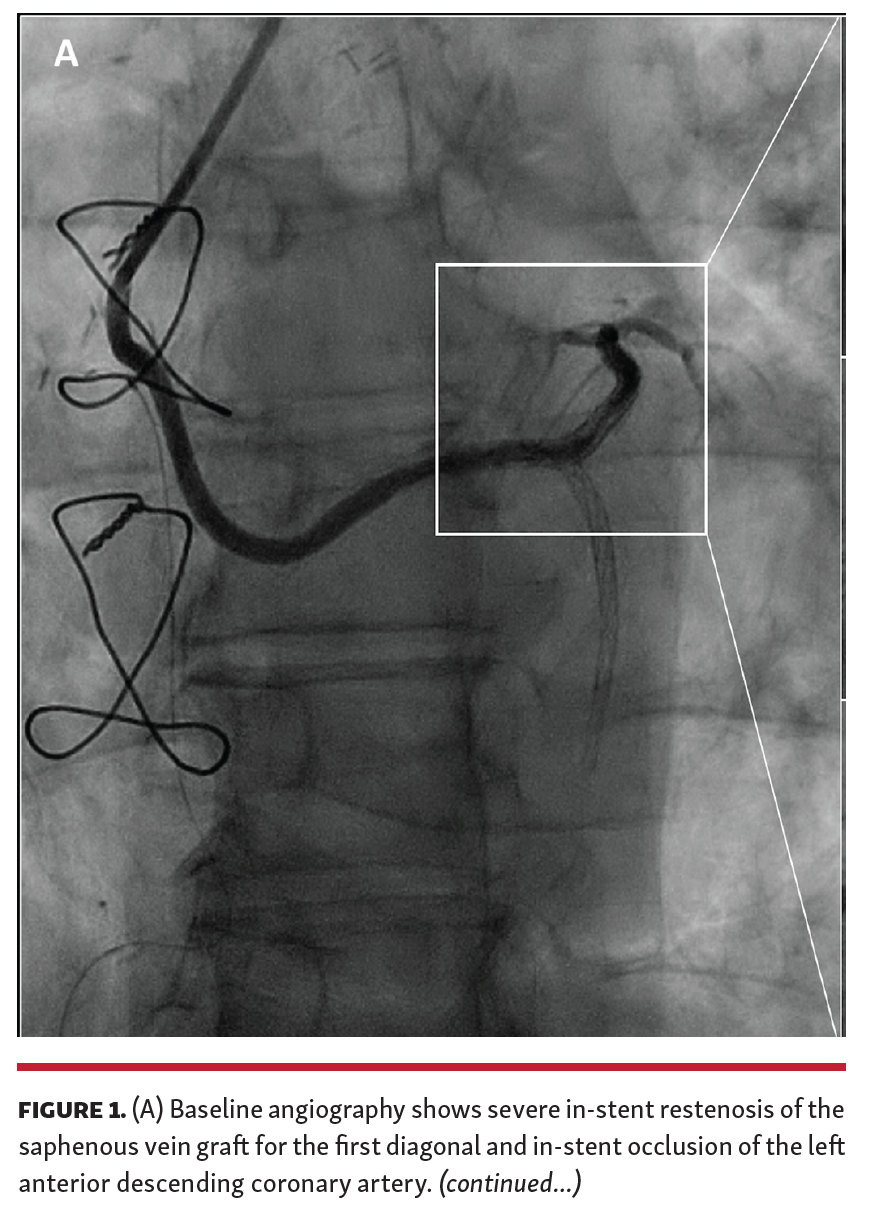

A 69-year-old man with prior history of coronary artery bypass graft surgery with saphenous vein graft (SVG) for the left anterior descending (LAD) and jump to the first diagonal (D1) underwent multiple percutaneous coronary interventions with drug-eluting stent (DES) implantation on the graft, due to aggressive in-stent restenosis (ISR), and on mid-distal LAD with multiple stents resulting in in-stent chronic total occlusion with no recanalization options because of inability to visualize the distal vessel. The patient was admitted to our institution due to worsening effort angina. He was already on optimal medical therapy. He underwent coronary angiography via radial approach, which showed subocclusive ISR in the SVG (Figures 1A and 1B). Patency of the other grafts was documented and no other revascularization target was identified. Intravascular ultrasound (IVUS) showed 270°, severely calcific ISR with at least 2 layers of previously implanted stent struts (Figure 1C). Considering the severe lesion calcification and perforation after non-compliant balloon dilation during a prior procedure, we decided to perform intracoronary lithotripsy. A 3.5 mm intravascular lithotripsy balloon (Shockwave Medical) was used and 8 balloon inflations were performed with IVUS documentation of cracked calcium (Figures 1D and 1E). After 3.5 mm non-compliant balloon dilation, a new-generation 3.5 x 20 mm DES was implanted and postdilated with good angiographic result (Figure 1F). IVUS showed acute gain in minimal luminal area (Figure 1G).

To the best of our knowledge, this is the first description of IVUS-guided coronary lithotripsy on SVG because of severely calcific ISR, showing good result without procedural complications. Additional increase in minimal luminal area was documented after stent implantation, as reported in the DISRUPT CAD II study. In our case, IVUS had an important role in assessing the severely calcific nature of the lesion, guiding treatment strategy in terms of choosing advanced debulking technique, and achieving optimal result. Optical coherence tomography could be superior in detecting superficial calcification due to better resolution, and reported up to 78% of cracked calcium in the DISRUPT CAD II trial. Future mid- and long-term studies are warranted on treatment of such lesions.